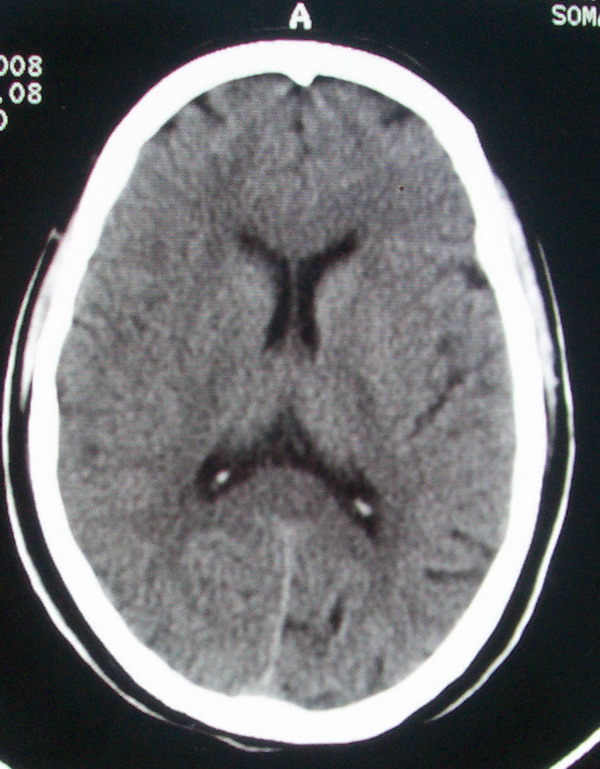

标题: CT13599:大家看是正常还是软化灶?已经重新上传 [打印本页]

标题: CT13599:大家看是正常还是软化灶?已经重新上传

这次用的是数码相机拍的,还是比手机拍的好。

脑沟,与下一层面连续.

正常脑沟。